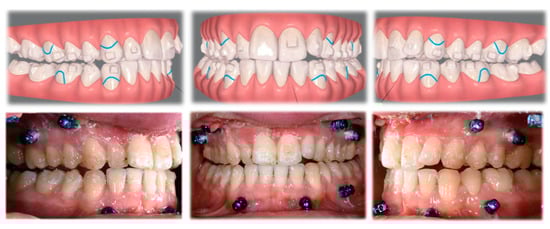

2.2. Clinical Preparations

| 1 month pre op | Invisalign attachments placed, any fixed orthodontic retainers removed and passive aligners were given to the patient. |

| 1 week pre op | Buttons were placed on the planned teeth and fixated together with a steel ligature wire. |

| Surgery | Tads and corticotomies performed during the orthognathic surgical procedure. |

| 1 week post op | Buttons removed and patient instructed in using active aligners. |